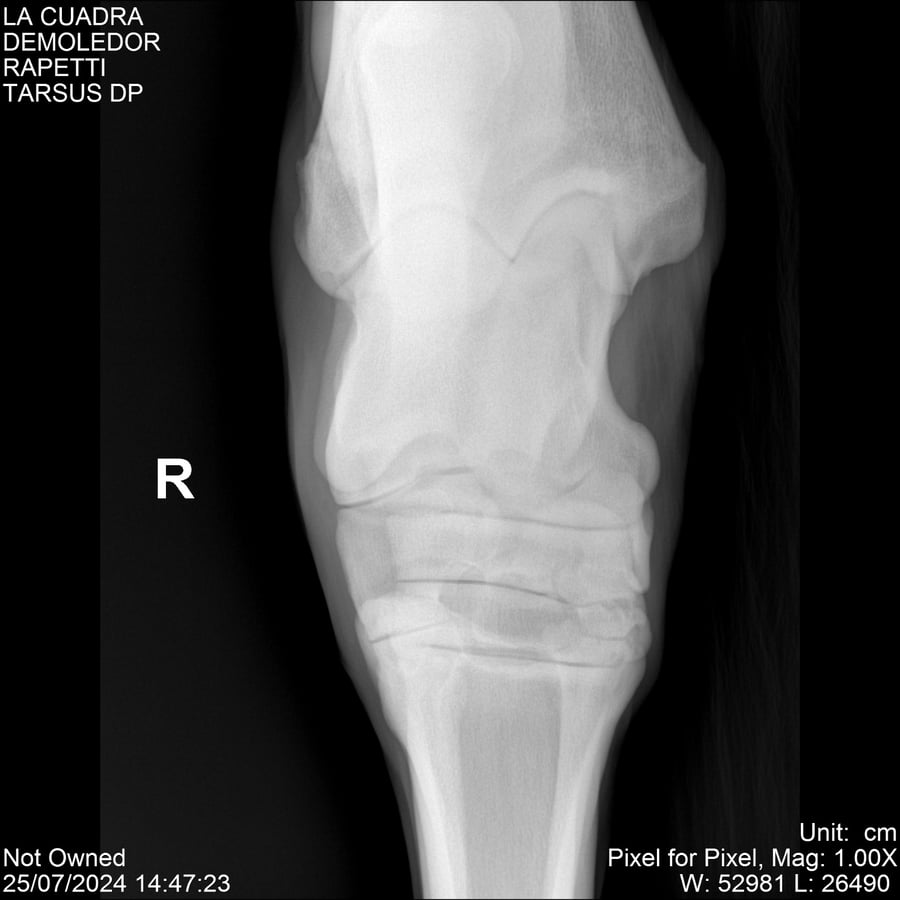

LOTE 14, DEMOLEDOR 🔥 🔥 🔥 Lote Anterior Volver al remate Lote Siguiente Ficha Contacto Montevideo - Ficha del Lote Identificador: #284454 Categoría: Yeguarizos Montevideo - 89 Visualizaciones ClicData Contacto Empresa: Abelenda N. R., Walter Hugo Nombre*: Teléfono* : E-mail* : Mensaje Enviar Registrese gratis Este contenido Exclusivo está disponible sólo para usuarios registrados Ingresar